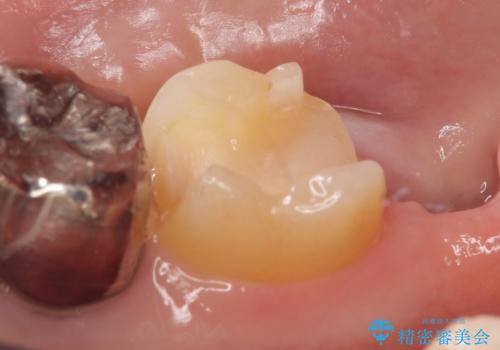

- 冷たいものを飲むと右下の奥歯が痛むので診て欲しいといらっしゃった方の症例です。

銀歯及び虫歯を除去後、より適合の良いPGA(ゴールド)インレーによる修復を行いました。

ゴールドは化学的な安定性が高いため変色や腐食がほとんどなく、アレルギーなども起こりにくい人体に優しい素材です。

また硬さも天然歯に近いため周囲の歯への影響も少なく、さらに適合もよいため虫歯の再発も少ない、とても補綴に適した材料です。